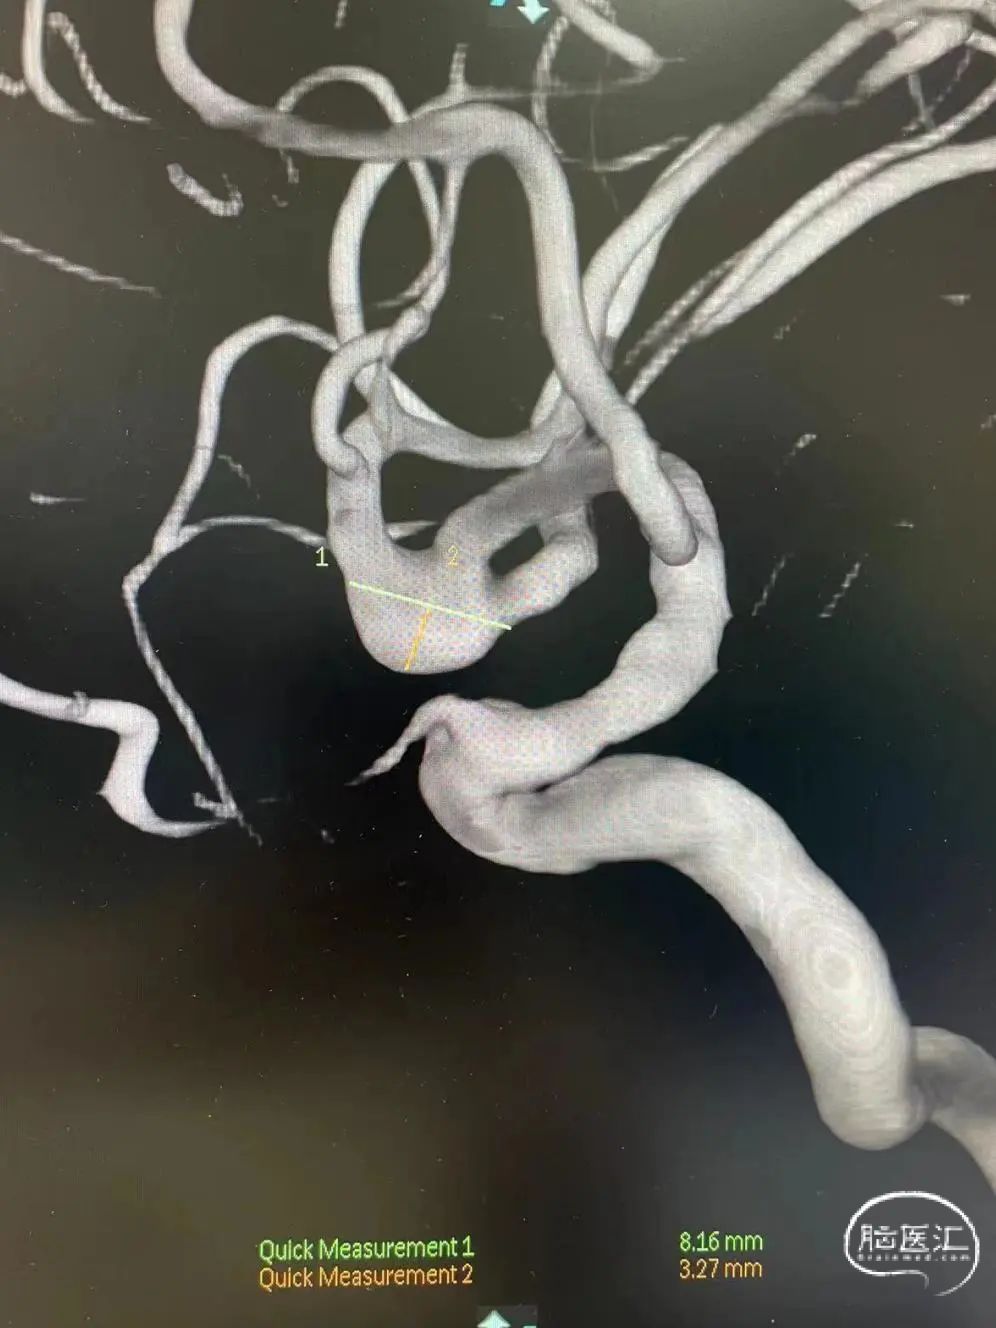

术前MRA显示右侧MCA分叉部囊状动脉瘤,具体解剖细节不详。

术前三维测量显示瘤体大小,瘤体约8.16mm*3.27mm,累及上下干, 上干约2.43mm,下干约3.56mm。